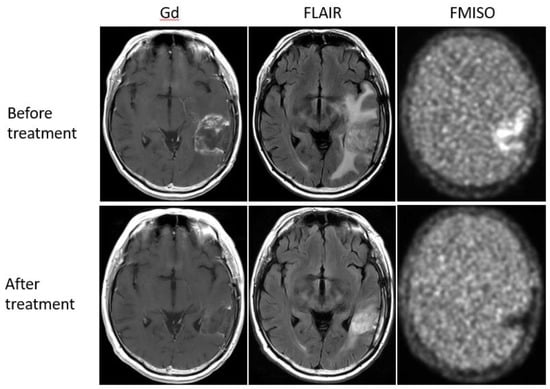

Figure 5. A 47-year-old patient with glioblastoma showed a strong uptake of FMISO before the bevacizumab treatment (upper row), but the FMISO uptake disappeared after the treatment (lower row). This patient was considered a ‘MRI-FMISO double responder’.

Bevacizumab is a recombinant humanized monoclonal antibody that blocks angiogenesis by inhibiting vascular endothelial growth factor A (VEGF-A) [58]. Although bevacizumab failed to prolong the overall survival of patients with primary glioblastoma [59,60], it was effective in some populations of recurrent glioma patients. In our retrospective study, we investigated whether FMISO PET has the potential to distinguish responders to bevacizumab from non-responders [61]. Eighteen patients with recurrent glioma underwent bevacizumab treatment. We compared the patients’ pre-and post-MRI and FMISO PET to classify them as (1) MRI-FMISO double responders (n = 9, Figure 5), (2) MRI-only responders (n = 5, Figure 6), and (3) non-responders (n = 4, Figure 7). There were no FMISO-only responders. The survival analysis demonstrated that the MRI-FMISO double responders had significantly longer overall survival than the other patients, whereas no significant difference was observed between the MRI-only responders and the non-responders. We thus concluded that recurrent gliomas with decreasing FMISO accumulation after short-term bevacizumab application could derive a survival benefit from the treatment.